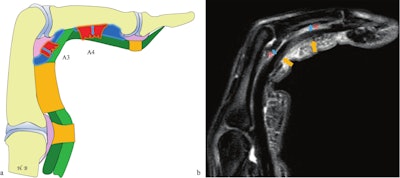

Finger in flexion against resistance. Combined complete rupture of the A3 and A4 pulleys. (a) Schematic illustration. (b) Sagittal proton density fat-saturated (PD FS) MRI. Fluid effusion (asterisk) and increased distance between the flexor tendon and the volar plate at the level of the joint (double-headed blue arrow) confirm injury to the A3 pulley. Fluid effusion (asterisk) and separation between the middle phalanx (P2) and the tendon (double-headed blue arrow) indicate additional injury to the A4 pulley. Note the edematous infiltration of the A3 and A4 pulleys located superficial to the flexor tendons (orange arrows).Bouredoucen et al; EJR